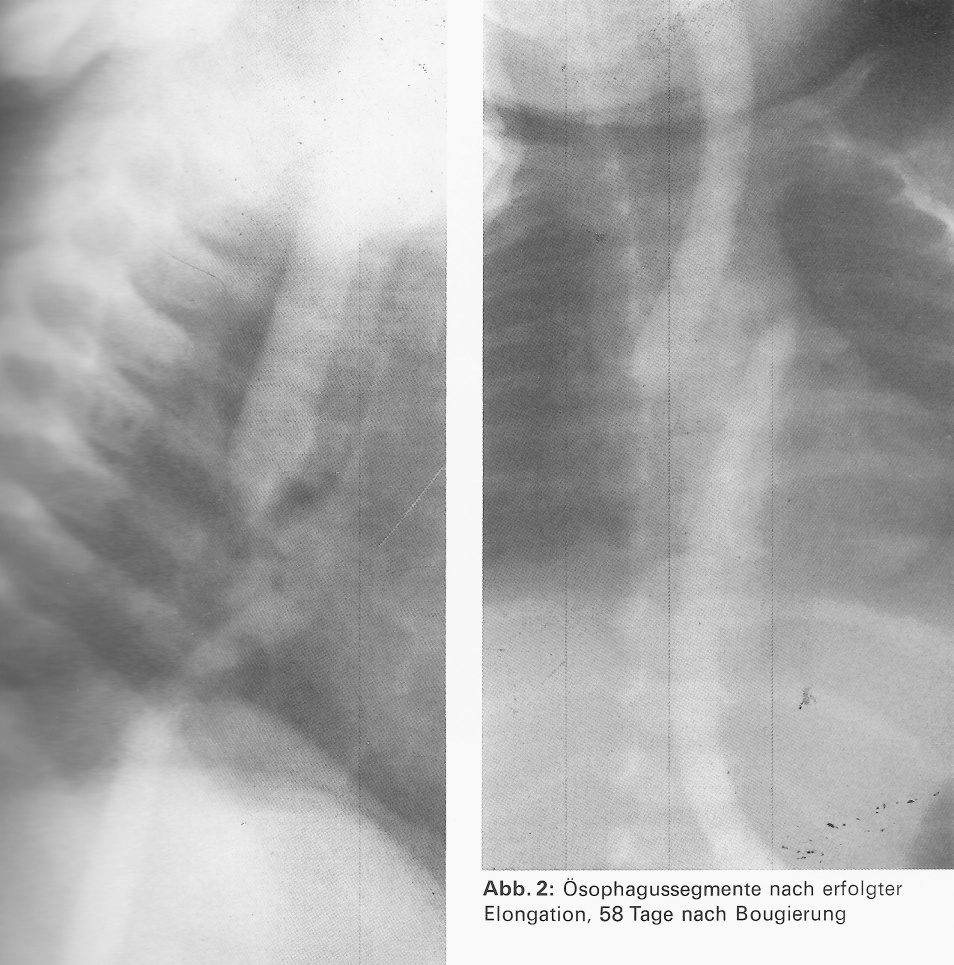

Unabhängig von Hays et al.*8 und Howard u. Myers*10 war von Haße*6 eine eigene Bougierungsmethode entwickelt worden. Seit 1967 wurden bei 5 Neugeborenen mit einer Typ II Ösophagusatresie nach Vogt beide Segmente –gastrales via Gastrostomie – bougiert,bis sie sich ohne Druck um 1-2 cm überlappten.

| Abb. 19: F. Rehbein | Abb. 20: Segmente 58 Tage nach Bougierung (04.1975) Die Segmente sind adaptiert. Eine End-zu-Endanastomose ist jetzt möglich. |

Als Spätkomplikation trat bei diesem inzwischen 36 jährigen Pat. eine Ösophago-broncho-pulmonale Spätfistel. Diese wurde in der Chirurgischen Universitätsklinik Hamburg-Eppendorf 2001 operativ geschlossen.

Booß*2 berichtete auf dem 2. Berliner Symposium 1990 über 17 Kinder, die in Bremen, Mainz und Berlin-Wedding nach dieser Methode behandelt worden sind. Trotz des Auftretens eines korrigierbaren Refluxes bei 7 Kindern hielt er, ebenso wie wir, diese Therapie für die Methode der Wahl.